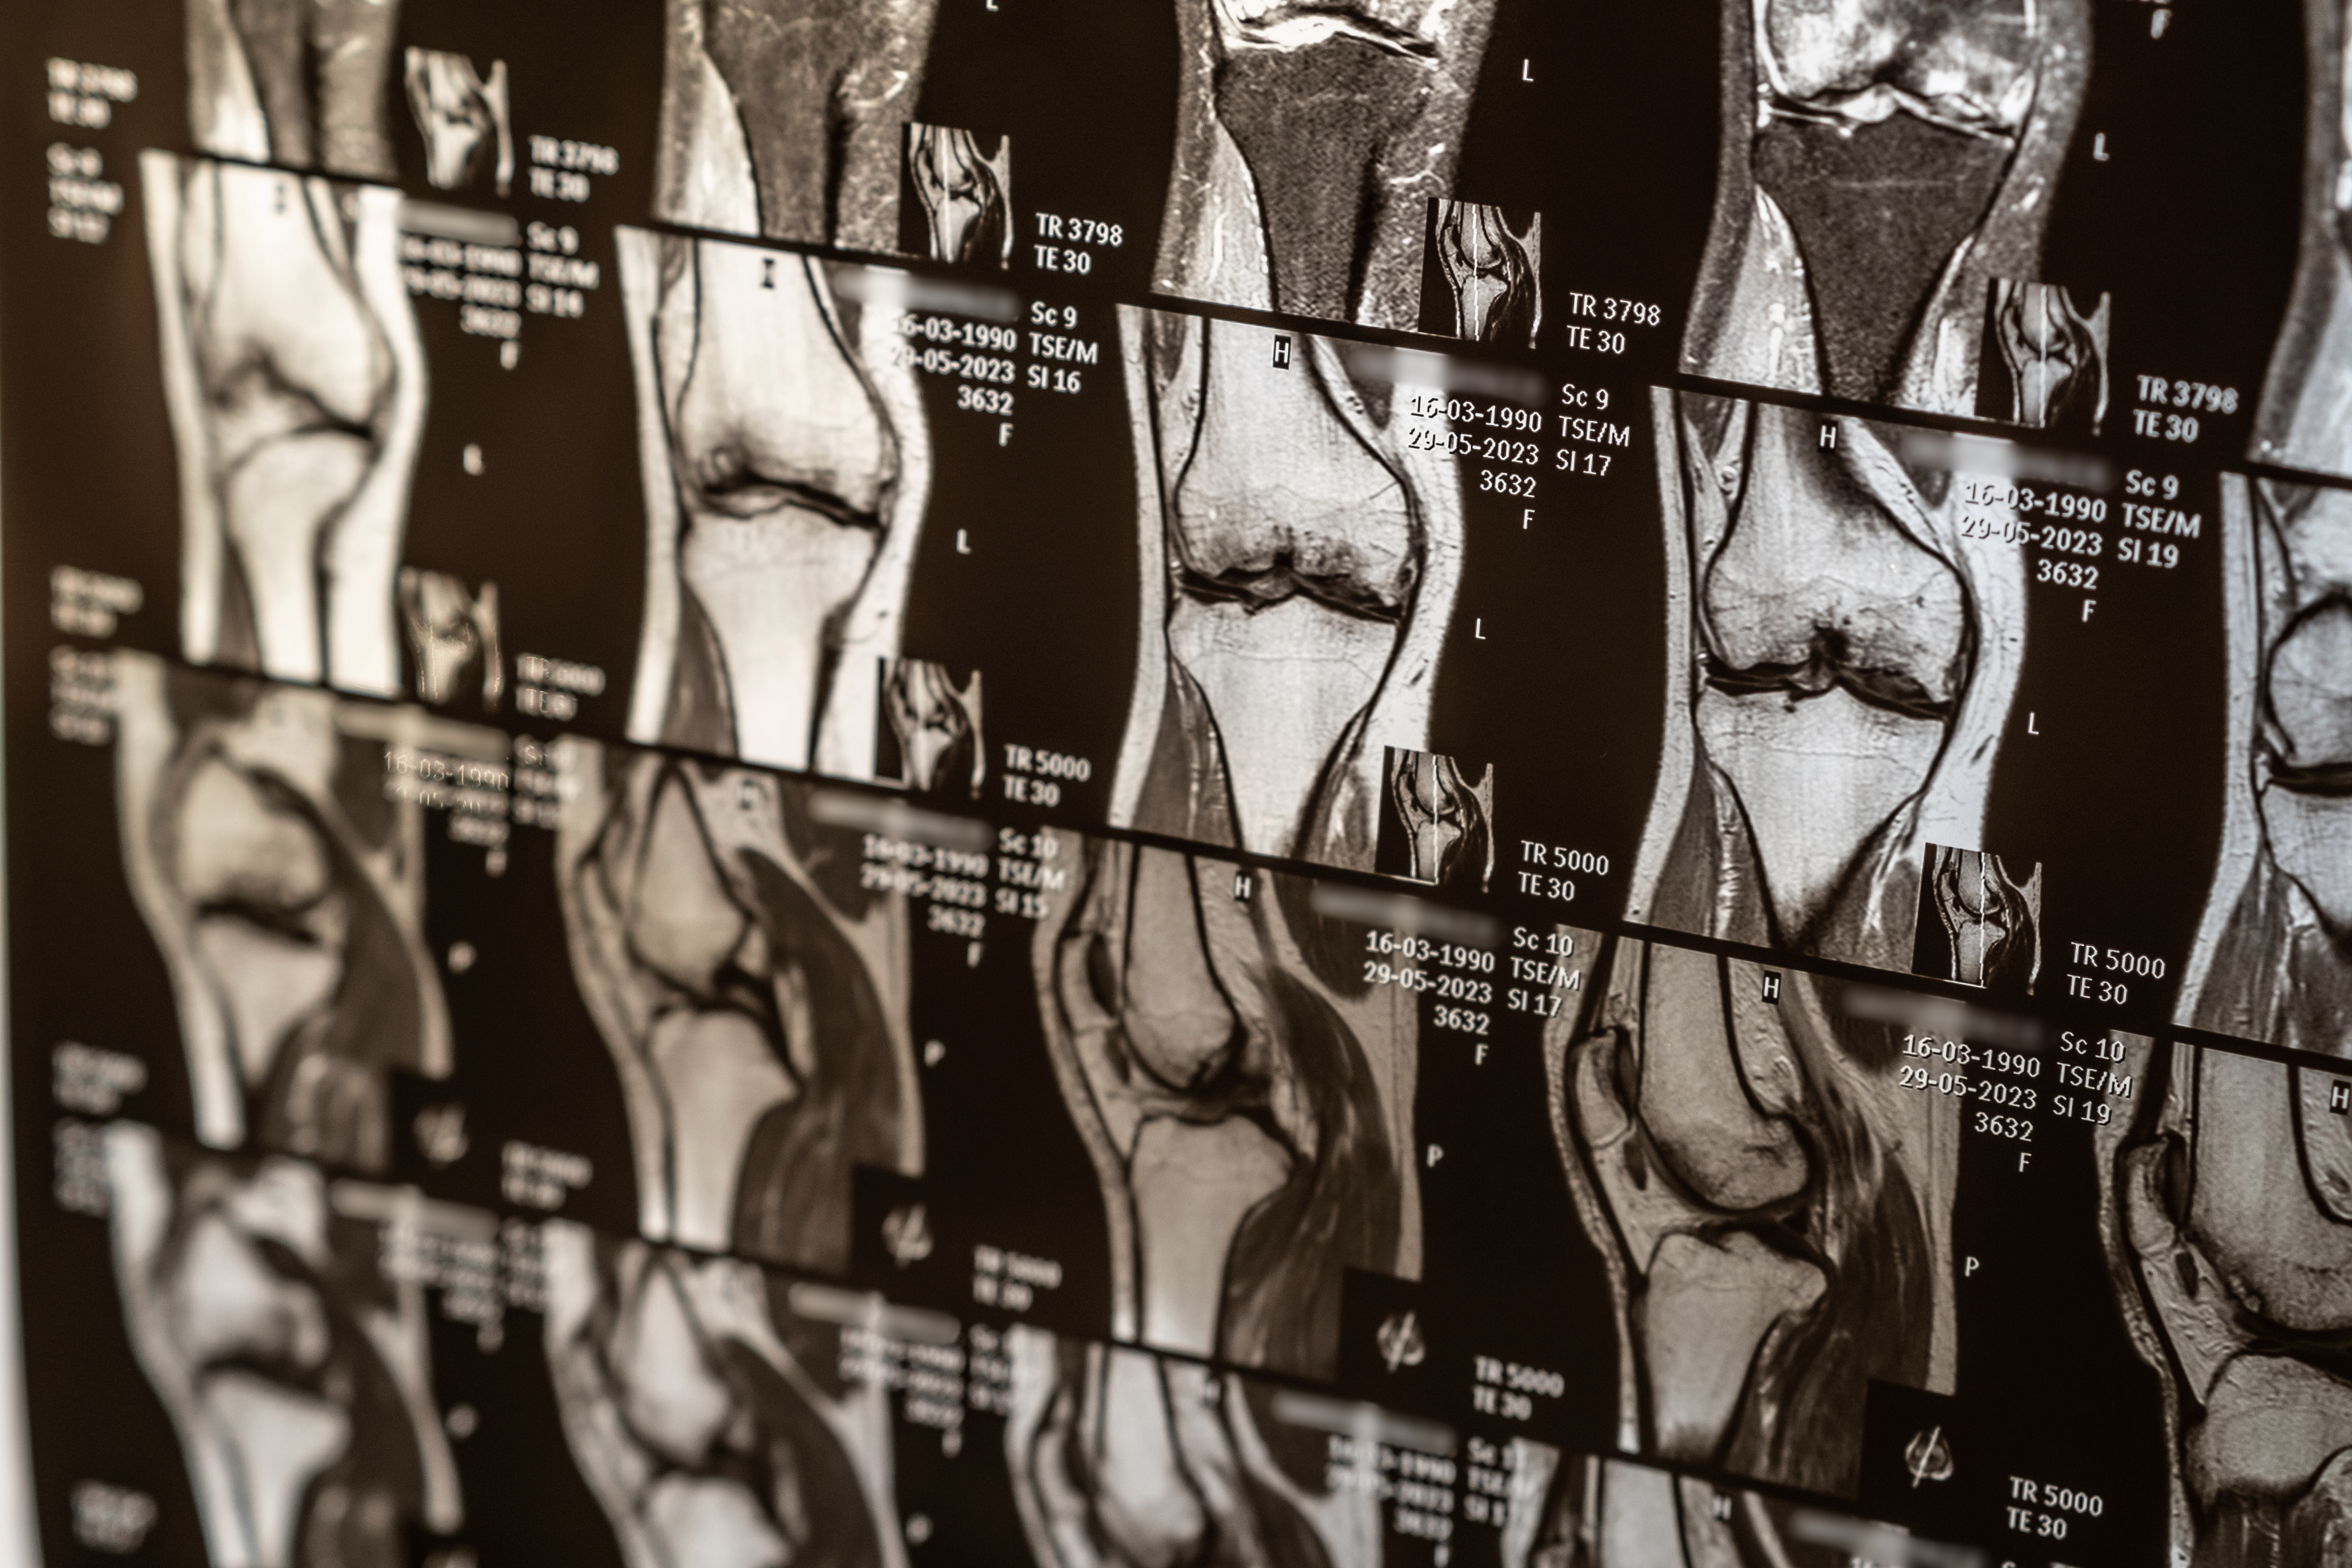

Here’s where things usually go off track. Many treatment plans are built around imaging results like X-rays or MRIs, or based only on symptoms like pain when running, kneeling, or sleeping. Sometimes, the plan is simply based on what’s most available at the time. What’s often missing is a deeper look at timing, movement patterns, and how ready your body actually is to heal.

Not always. Imaging like MRIs can show structural changes, but they don’t always explain why you’re in pain. Many people have abnormal findings without symptoms. Your pain needs to be understood in the context of movement, stability, and overall body function.Are injections enough to fix knee pain?